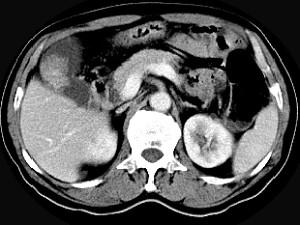

问题 男,45岁,右季肋区疼痛,Murphy征阳性,B超提示胆囊息肉,CT所见如图,最可能的诊断是 ( )

选项 A、胆囊转移癌 B、胆囊腺肌增生症 C、胆囊癌 D、慢性胆囊炎 E、胆囊息肉

答案 C